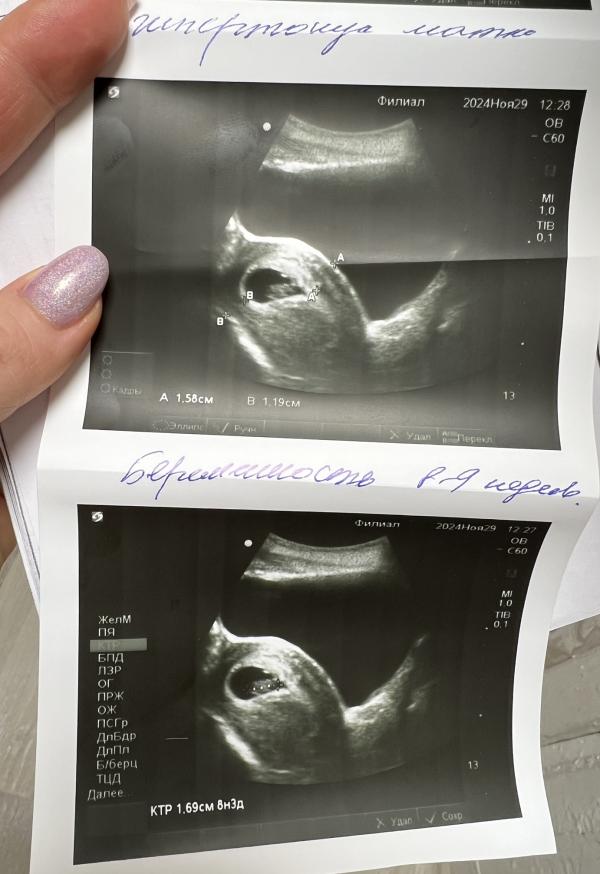

Гипертонус 2 степени на УЗИ: угроза, но самочувствие хорошее?

post image 1

post image 2

Пятое узи!

Гипертонус, 2 степень, ставят угрозу. Сама я его не ощущаю🤷‍♀️

В остальном все хорошо!

малыш развивается отлично, все по сроку 🥰